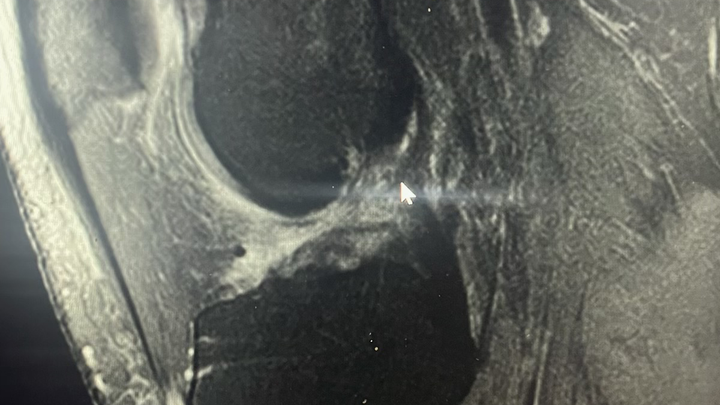

Some of you may know, but I took a fairly bad fall at work while in the kitchen and damaged my knee significantly enough to require surgery. Any money that is donated will be going towards medical costs that insurance won’t cover. On the 1st of July, I'm having an Arthroscopic Assisted ACL Reconstruction With Quadriceps Tendon Autograft, Medial And Lateral Meniscus Repair, and Osteochondral Lesion Repair With Cartiheal Agili-C Implant.

The attached photo is an MRI of my knee showing my ACL (or lack thereof lol)